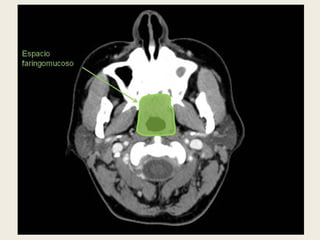

ESPACIO MUCOSO FARÍNGEO.

 Se localiza medial al espacio parafaríngeo y se

delimita por la capa media de la fascia cervical

profunda. Contiene el tejido linfoide del anillo de

Waldeyer, glándulas salivares menores, fascia

faringobasilar, músculo constrictor medio de la

faringe, músculo elevador del velo del paladar y

torus tubárico (cartilaginoso).